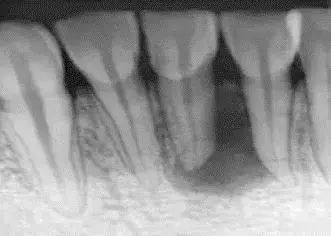

根尖周脓肿

根尖周脓肿是患者的牙髓炎没有及时治疗好,导致患者的根尖周组织受到了感染,然后出现了脓包。